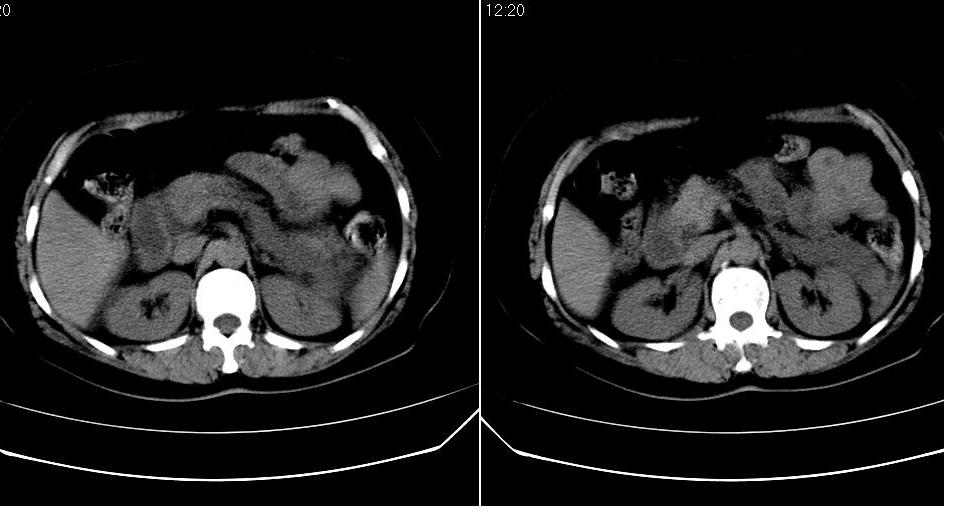

女 52岁,腹痛两天,无其它不适。

左肾周筋膜增厚,肾前间隙积液,胰腺肿大,胆囊结石,胰腺炎

胆囊结石 胰腺炎伴胰尾假性囊肿形成.

胆囊结石,胆总管结石.胰腺炎,胰尾假囊肿形成.

胰头部囊状影是十二指肠。左侧肾前筋膜增厚、少量积液,胰腺增大,边缘模糊,支持胰腺炎。

1、慢性胆囊炎,胆囊结石、胆总管结石。诊断依据:胆囊内、胆总管内见高密度影,胆囊已有萎缩,说明时间已较长,胆囊壁有增厚。

2、胆源性胰腺炎,诊断依据:同1外+左肾周筋膜增厚,肾前间隙积液,胰腺肿大。